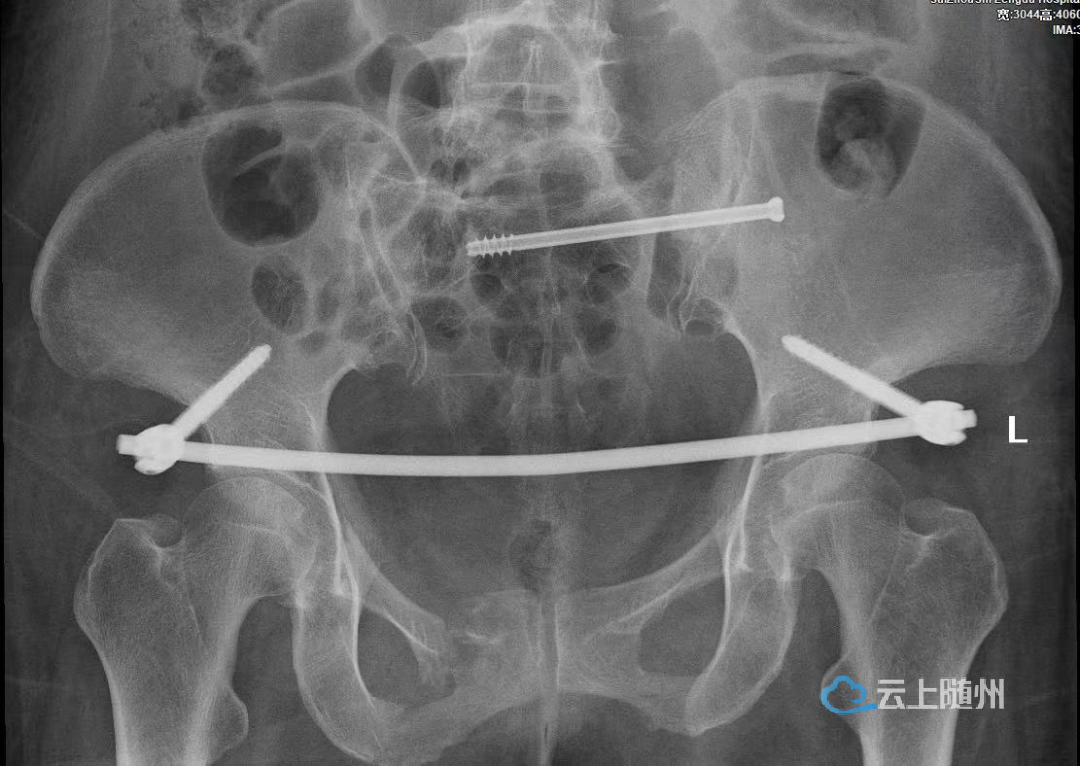

近日,随州市曾都医院关节、创伤、神经外科医护团队成功为一骨盆骨折合并Morel-Lavallée损伤患者实施骨盆骨折InFix 固定+骶髂关节螺钉内固定手术。

患者创伤严重,骨盆前后环垂直旋转不稳定,手术难度和风险都很高。关节、创伤、神经外科主任周强高度重视,考虑到传统的骨盆外固定,钉道口容易感染,体外装置对日常活动存在较大影响,固定稳定性较内固定存在差别,早期下床易出现骨折移位及易造成患者心理负担等缺点。经过医护团队多次讨论后,决定为其在全麻下行骨盆骨折InFix 固定+骶髂关节螺钉内固定,征询患者及其家属同意后,于6月1日在华中科技大学附属协和医院骨科郭晓东教授的指导下,顺利完成手术,目前患者恢复良好。

骨盆骨折InFix 固定+骶髂关节螺钉内固定手术的成功开展,填补了曾都医院骨盆骨折的微创空白。它具有手术时间短、切口小、出血少、恢复快、费用低、外观良好等优点,而且术中不破坏骨外膜,固定稳定性和切开复位钛板内固定无差异;术后不需要放置引流管,有利于骨折愈合,患者满意度高。